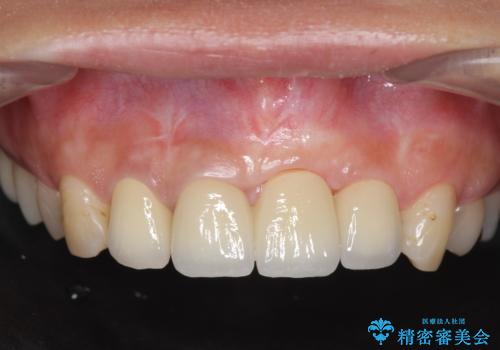

不良インプラントの除去・骨造成・歯肉移植・前歯審美セラミックブリッジ製作

不良インプラントを除去し最終的にブリッジによる補綴で審美性の改善を行うこと、その準備として骨の造成・歯肉の移植による歯の欠損部顎堤のボリュームを維持・増大を計画します。

より審美的な改善を強く求められたため、インプラントを除去し可及的に欠損部顎堤を増大したのちブリッジによる審美改善を行いました。